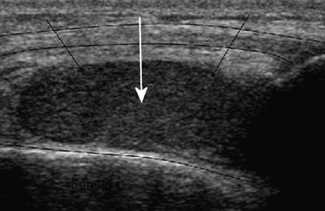

Reflection is a very important property of sound waves, as it provides echoes at tissue boundaries, and these are used to depict structures in diagnostic ultrasound. It also gives some information about the nature of tissues. A cyst, which mostly contains fluid, will return few or no echoes (the signal is termed hypoechoic or anechoic) from within itself, as shown in Figure 42.1, while a haemorrhage will return echoes from within itself (the signal is echoic or hyperechoic), as shown in Figure 42.2. This is because a haemorrhage also contains blood cells and proteins (which return echoes) in addition to just fluid. The walls of a cyst may return strong echoes at the capsule–fluid boundary.

Figure 42.2 This haemorrhage into a joint returns many small bright echoes from the substances within it, such as blood cells and proteins. It is echogenic (echo producing).